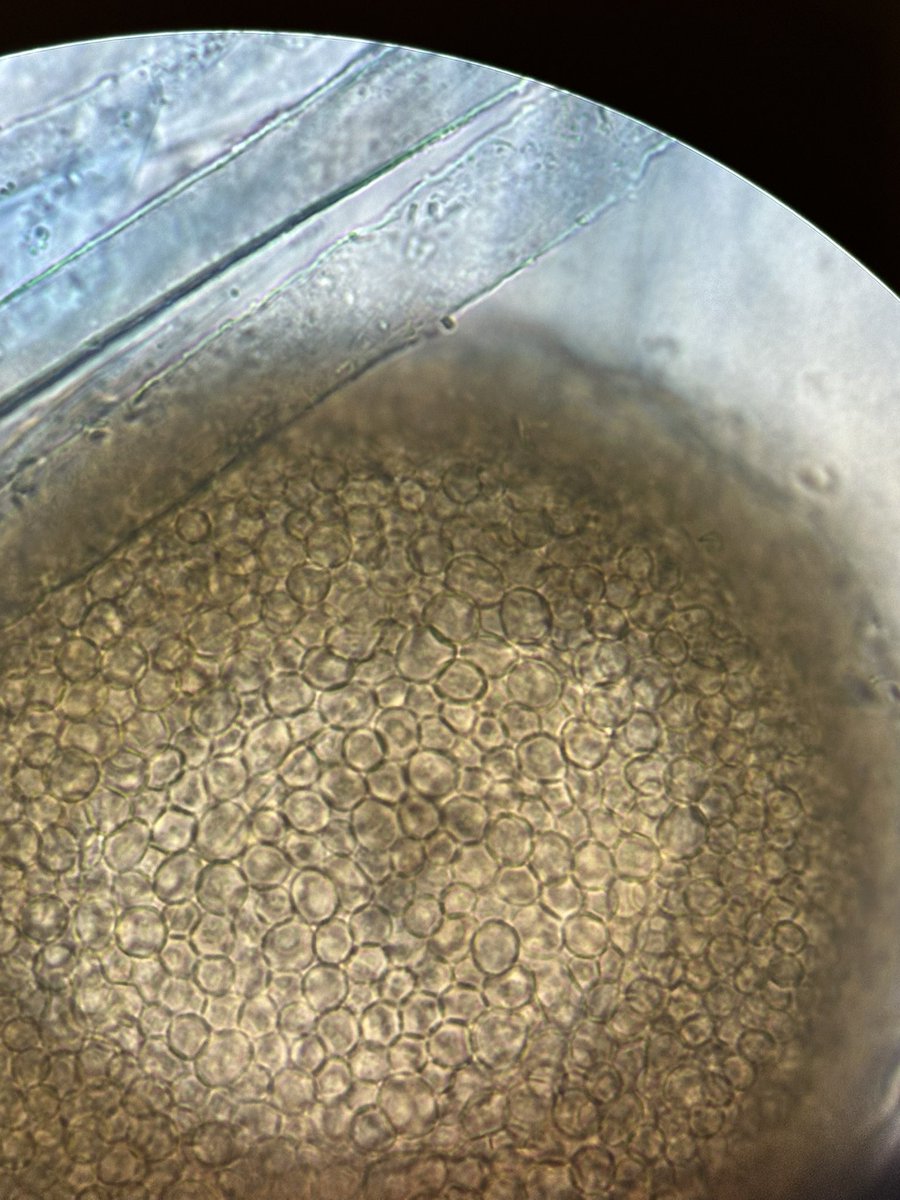

@infectotuits We also had a #MucorMonday over here

#FungiFriday Un placer compartir unos minutos y aprender de usted Tom Chiller En el curso de Micosis del INCMNSZ